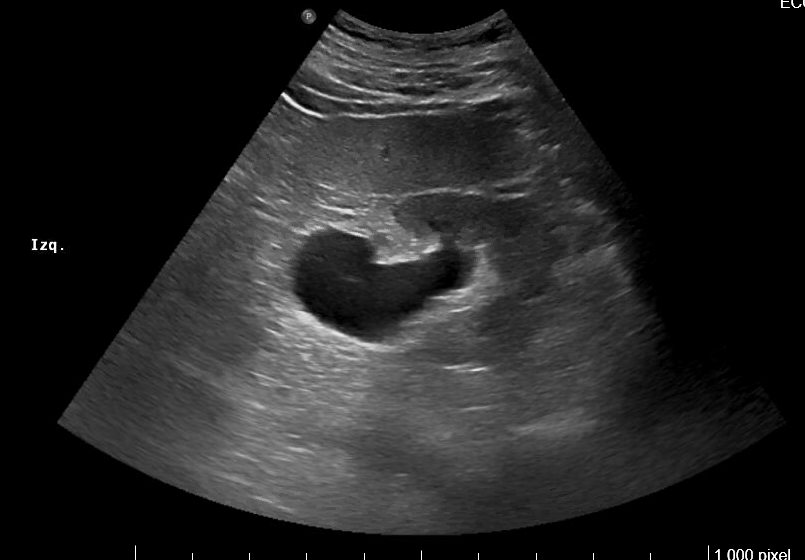

Imagen 1. Riñón derecho: hidronefrosis grado II. Tamaño 11.2 cm.